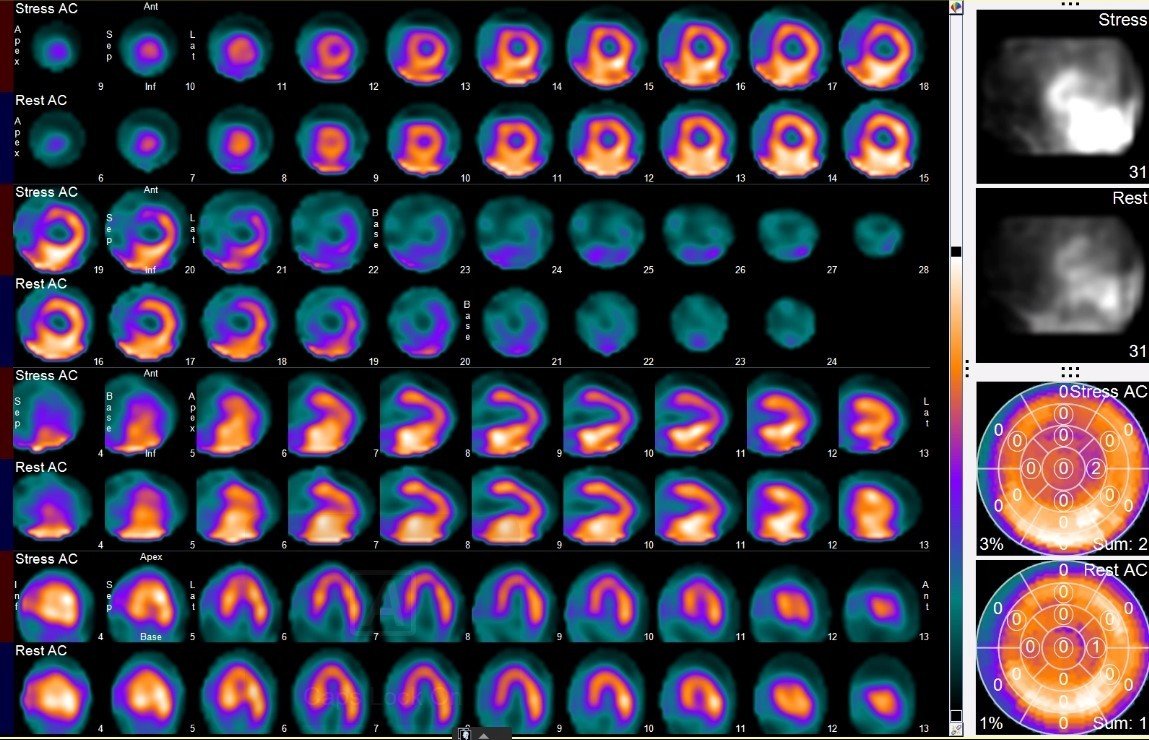

MPI

The myocardial perfusion is unremarkable with no evidence of prior infarct or significant ischemia. Note is made of decrease from rest EF of 60% to post-stress 52% of indeterminate significance.